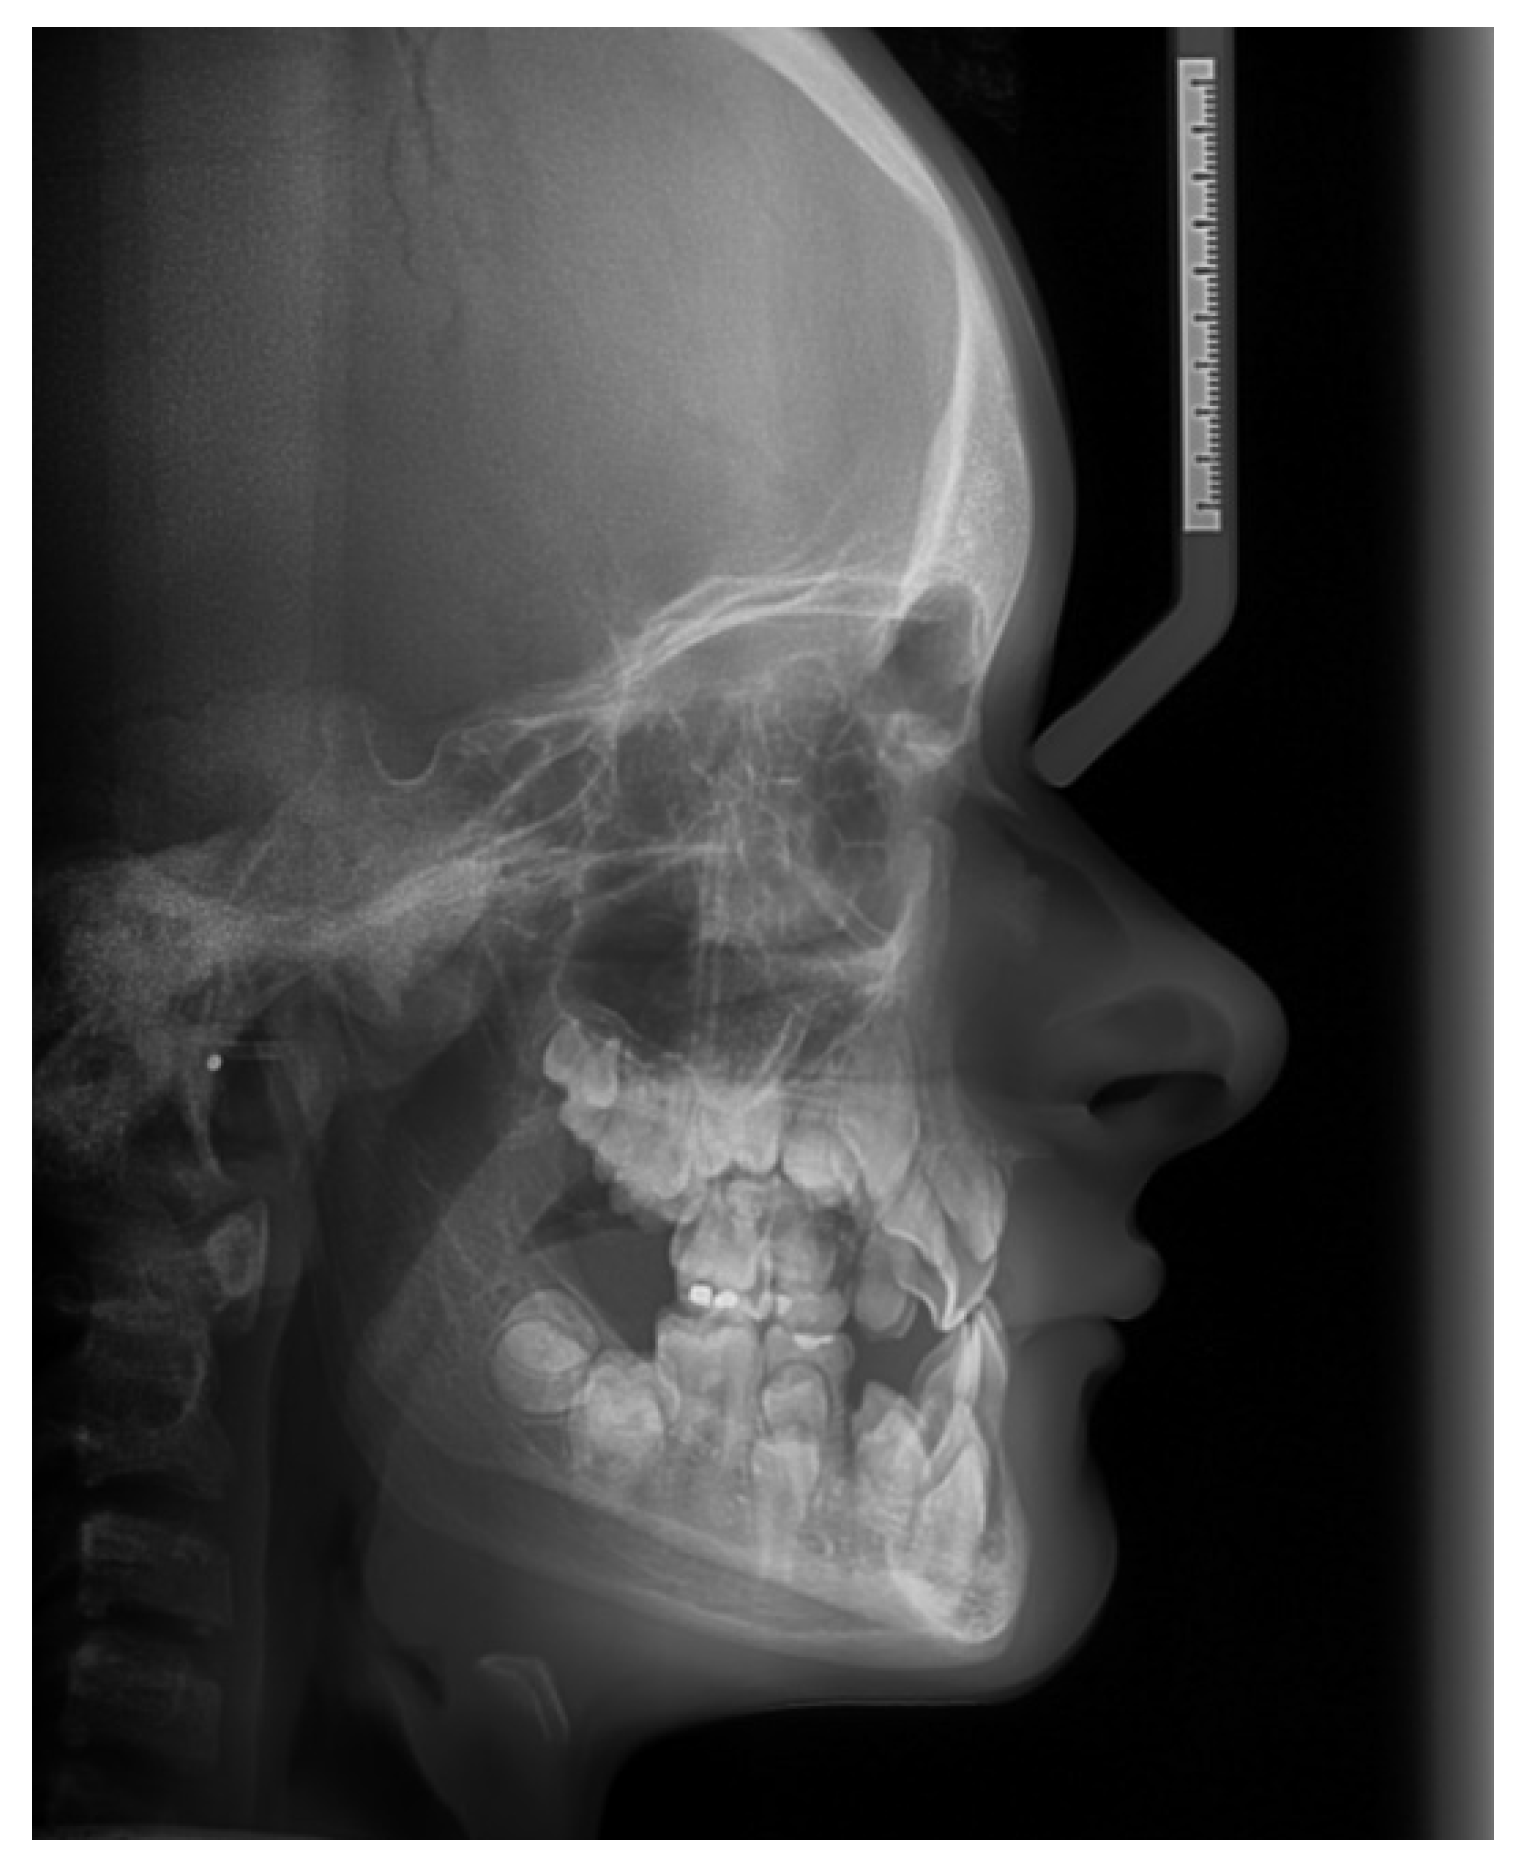

Figure 13. Pretreatment lateral cephalometric radiograph. The analysis of the cephalometric x-ray revealed. a normal saggital relationship of the jaws. Note the delayed fusion of fontanels.

In June 2019 the patient was first examined at the Orthodontic department of the Clinic of Stomatology of Teaching Hospital in Hradec Králové. A cephalometric x-ray was taken and an up-to-date panoramic x-ray -OPG. Orthodontic impressions were taken and both a cephalometric x-ray and a cast model analysis were executed.

Cephalometric Analysis

The results of the cephalometric picture analysis were promising. (Figure 13.) The relationship in the saggital position of the jaws was in the Ist Class, (ANB 1,4° and the Wits appraisal – 0,9 mm ) against our expectations. The CCD patients frequently have underdeveloped maxilla in all directions. The saggital position values of the anterior border of the maxilla and mandible (A and B) were enlarged, due to the underdevelopment of the sutures of the skull – the reference point N lies on the nasofrontal suture. The pronounced anterior crossbite was due to the very steep interincisal angle, (1+1- 166,5°) and the upper incisors were severely palatally inclined (1-NS 89,2°). The lower incisors were in correct position (1-ML 85,6°). There was a significant anterior rotational tendency of growth of the lower jaw (SGo/NMe 80% and the NS-ML 18,7°). (Table 1)

Craniofacial abnormalities are expressed in over 80% of the cases including skeletal Cass III tendency and mandibular prognathism and short anterior cranial base. [5] Thus it is important to critically analyze the appropriateness of using standard cephalometric values. [13] Despite hypoplastic maxilla, the cephalometric values have been contradictory normal, showing SNA angles close to 90°. The error emerges from the incorrectinterpretation of the point N (Nasofrontal suture) which is a basic reference point in the majority of cephalometric analyses. Provided that there is limited growth of the cranial base and depressed nasal bridge, the position of the Nasofrontal suture point is unusual and it is misleading to compare the position of both points A and B to it. [12] Thus it´s reasonable not to overestimate the results of SNA and SNB measurements and better interpret the ANB angle, and Wits appraisal. [12] Our patient had 1,4°of ANB angle, which is within normal ranges as well as the Wits which was -0,9°. This sign that there was no sign of Class III tendency, patient is saggitally well in Class I.

Although maxillary hypoplasia has been commonly described in CCD patients, cephalometric values have been contradictory, showing normal SNA angles. [5,12] The interincisal angle is usually significantly larger in CCD patients compared to unaffected individuals. There are marked lingual inclinations of lower incisors confirming the skeletal Class III tendency. [12]

Regarding the mandible, cephalometric analysis [12] results support the presence of a prognathic mandible. Clinically evident pseudoprogenia is due to marked midface hypoplasia rather than mandibular hyperplasia [12]. The anterior cranial base is short, leading to a posterior position of the nasofrontal suture. The whole midface of these patients is usually poorly developed. Reduced vertical development of the midface may lead to significant anterior rotation of the mandible. The vertical facial growth may be impaired due to reduced alveolar bone development. [5]

Beside the assessment of antero-posterior relationships, the mandibular hypodivergency has been consistently reported, where counter-clockwise (CCW) mandibular rotation was typical. Such forward rotation might be caused by a reduced vertical development of the midface, hypoplasia of facial bones, and underdevelopment of paranasal sinuses. Our patient manifested 80% of SGo/NMe angle which signs purely CCW rotational tendency, as well the NS-ML 18° angle.

The interincisal angle of CCD patients is usually larger than control groups. Our patient had 166,5° which corresponds with the findings of the CCD patients. [12] The lower incisors were almost in the correct position (1-ML 86,5°), so the reversed bite was almost entirely result of poor upper incisor inclination (1-NS 89,2°). After we have orthodontically aligned the upper incisor inclination, the correct overjet situation is established.